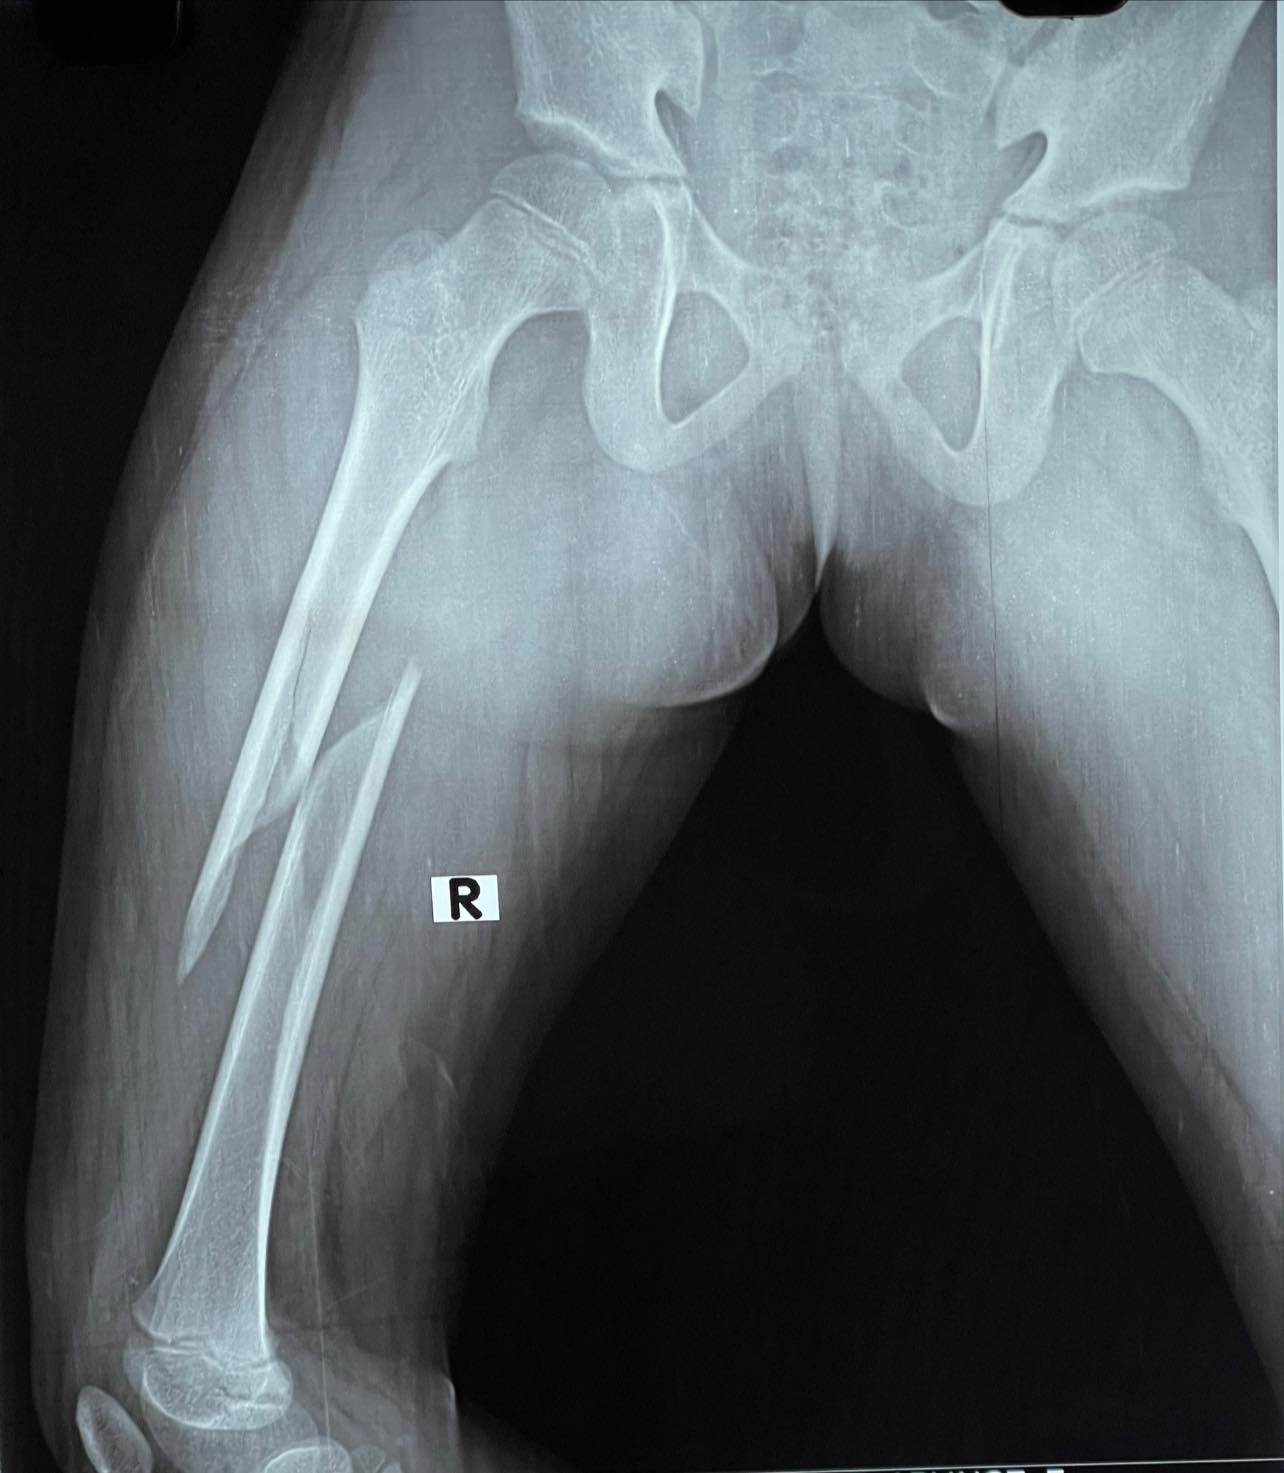

case in point: 6 yr old male with shaft of femur fracture treated with minimally invasive titanium elastic nails, in such cases, absolute picture perfect reduction is neither necessary nor often is possible, however, it would be hard for a surgeon to explain all this to the esteemed parar dada.

For all intents and purposes this will have a normal union and should leave no deformity or lasting future issues.